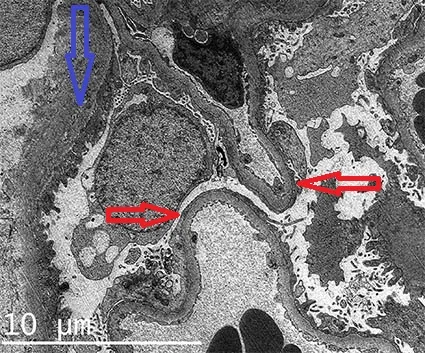

* **Electron Microscopy (EM)**:

* Deposits: Location (subepithelial, subendothelial, mesangial, intramembranous), density.

* Foot process effacement (common in proteinuria).

* GBM: Thickening, thinning, splitting (e.g., "basket-weave" in Alport).

- EM: Diffuse podocyte foot process effacement.

- EM: Foot process effacement.

- EM: Subepithelial deposits ("spike & dome").

- EM: Thick GBM.

- EM: Subepithelial humps.